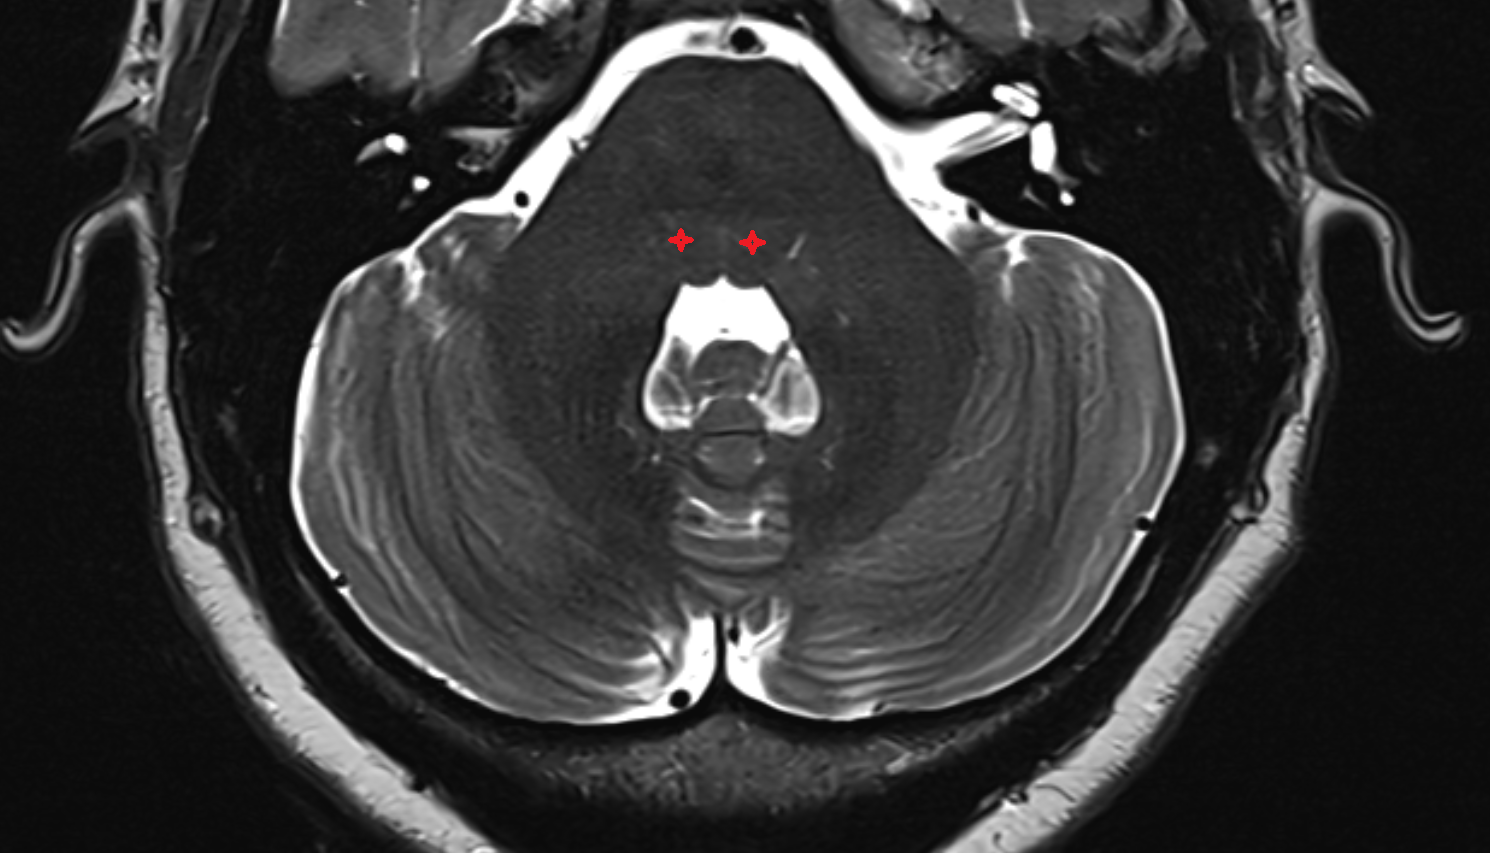

- Pons

- Fourth ventricle

- Cerebellopontine cistern

- Lateral aperture of fourth ventricle (foramen of Luschka)

- Sylvian cistern

- Pontocerebellar cistern

- Prepontine cistern

- Flocculus